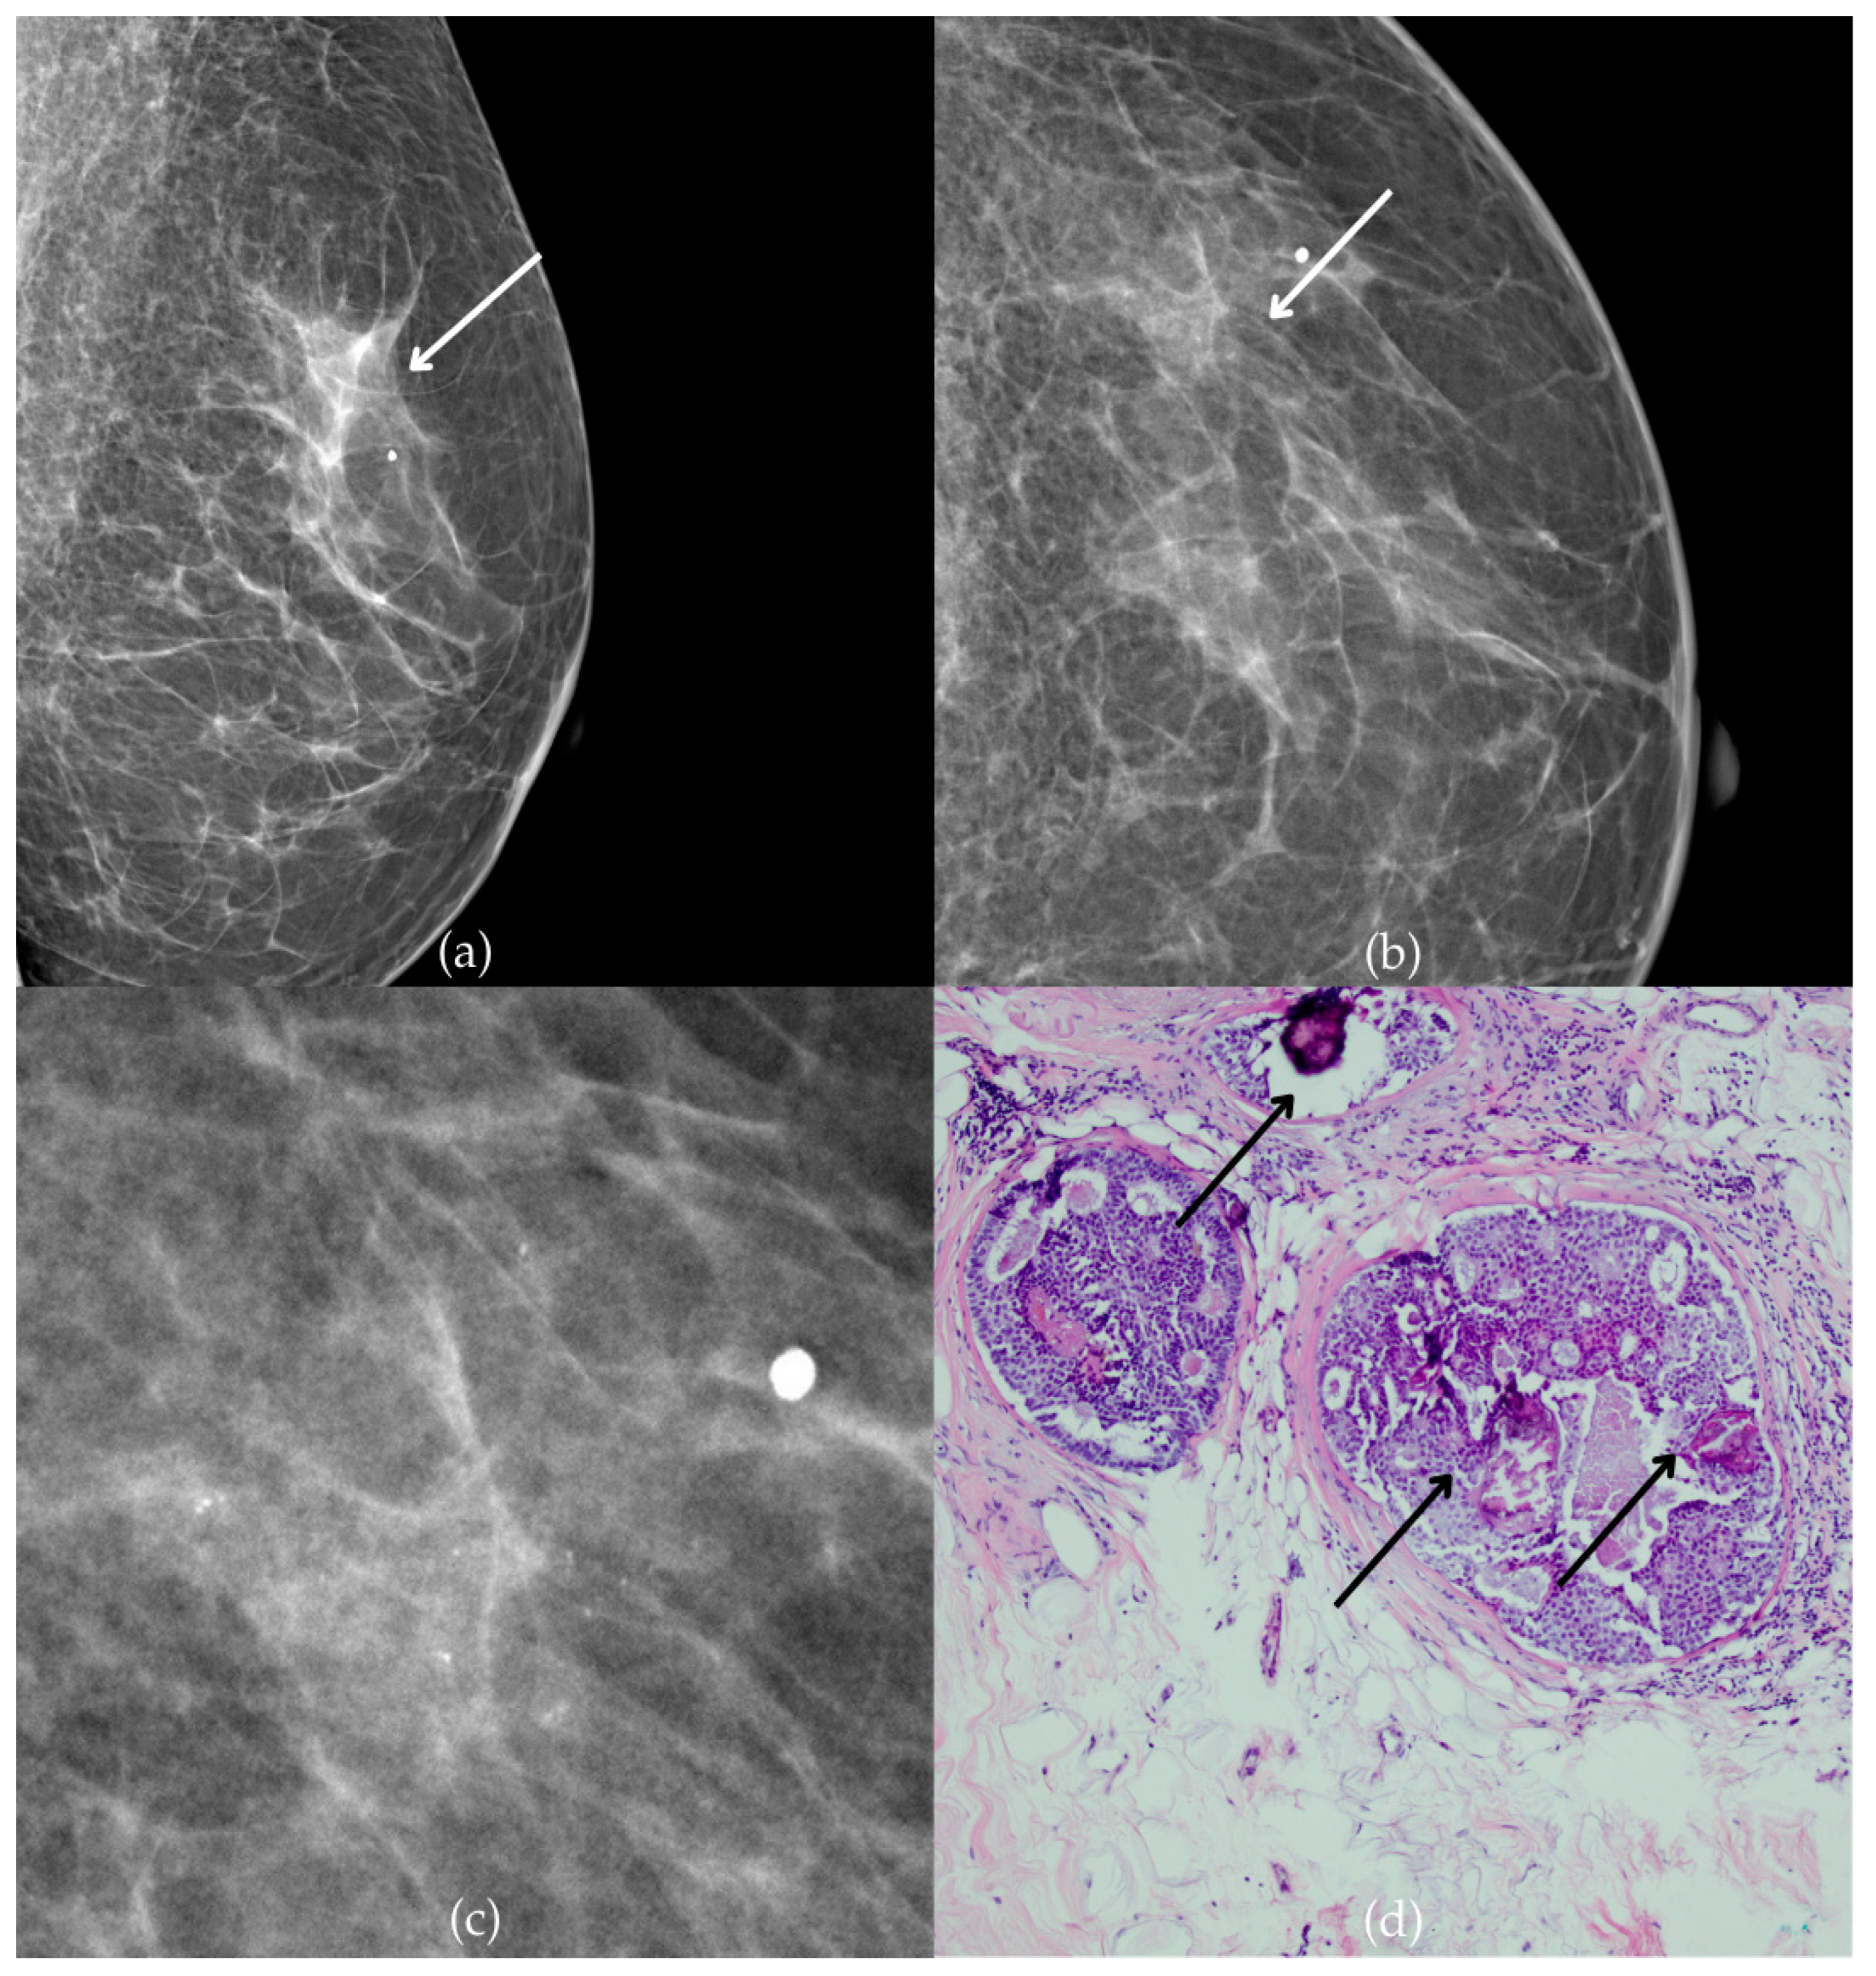

During a screening program, a 64-year-old patient presented with suspicious microcalcifications. The mammogram shown in Figure 3 of the patient’s right breast revealed a segmental distribution of coarse heterogeneous and fine pleomorphic calcifications in the upper outer quadrant, corresponding to a BI-RADS 4 finding. Tissue analysis obtained through VABB confirmed the presence of invasive carcinoma (category B5b). The patient underwent a mastectomy. Postoperative pathology showed only an in situ component, with no evidence of an invasive component, indicating that the invasive component was removed during the biopsy. One year after diagnosis, the follow-up US was reported as BI-RADS 2 classification, indicating benign imaging features.

Figure 3.

Invasive breast cancer. (a) Mediolateral oblique (MLO) mammography view; (b) craniocaudal (CC) mammography view of the right breast showing coarse heterogeneous and fine pleomorphic calcifications (marked with arrows) in the upper outer quadrant, with segmental distribution. (c) Magnified mammographic image of coarse heterogeneous and fine pleomorphic calcifications with segmental distribution. (d) The histopathological image of the biopsy sample shows the characteristic features of invasive cancer (marked with arrow) and ductal carcinoma in situ (DCIS) (marked with arrowhead) (HE staining; 40× magnification).